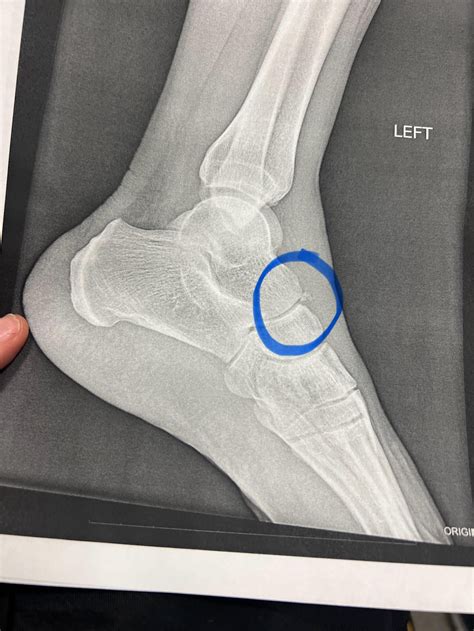

When you experience a sudden, sharp pain in a joint followed by swelling, you might be dealing with an avulsion fracture. This injury occurs when a small chunk of bone attached to a tendon or ligament gets pulled away from the main part of the bone. Unlike a typical break, this injury involves the soft tissue putting enough tension on the bone to cause a fracture at the attachment site. One of the most common treatments recommended by orthopedists is a cast for avulsion fracture, which serves to immobilize the affected area, allowing the bone to knit back together without the stress of daily movement.

Avulsion fractures are frequently seen in athletes, particularly those involved in sports requiring sudden changes in direction or explosive power. Common sites for these injuries include the ankle, hip, finger, and base of the fifth metatarsal in the foot. When a muscle contracts forcefully, it can pull on its tendon, and if the force is excessive, the bone simply gives way. Because the movement of tendons is constant, the primary goal of medical intervention is complete restriction. Using a cast for avulsion fracture ensures that the tendon does not pull the bone fragment further out of alignment while the healing process begins.

The severity of the injury often dictates the type of immobilization required. While some minor fractures may only need a walking boot or a splint, significant fractures usually necessitate a traditional plaster or fiberglass cast to ensure strict non-weight-bearing status. Failure to properly immobilize the site can lead to non-union or malunion of the bone fragment, which may eventually require surgical intervention.

Ankle (Malleolar) Fiberglass/Plaster Cast Restrict joint rotation and inversion